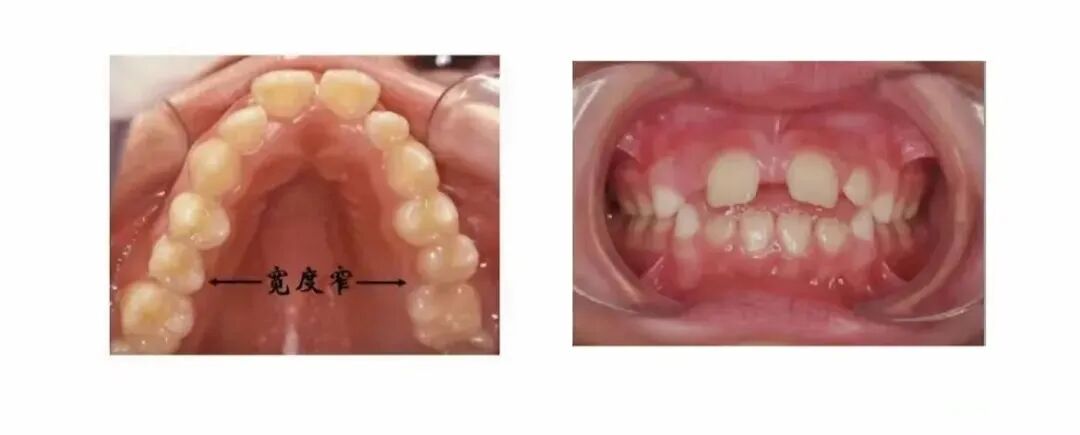

5.错合畸形

目前有观点认为舌系带过短或异常舌位,会造成错合畸形。正常的吞咽时,舌尖在上门牙后约5毫米的位置,舌体上抬,舌头贴在上腭。当舌系带过短,导致舌体无法上抬,容易形成习惯性舌低位,导致上颌牙弓狭窄。

舌系带短的孩子,舌体活动受限,吞咽时舌头抬不到上腭,而是抵着下前牙,导致地包天。

或者舌尖从上下门牙之间出来,导致开合。